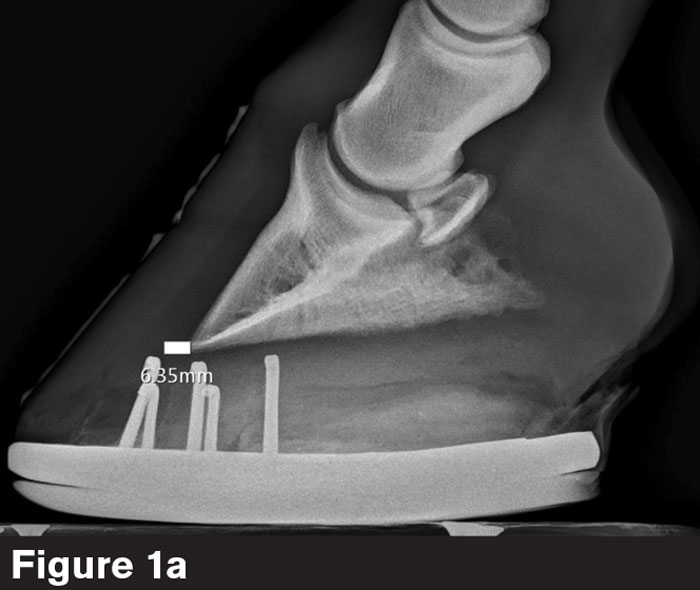

8. Block markers. Barrett wants to see only one coffin bone wing, one branch of the shoe (Figure 1a) or the correct block marker. Since he made his blocks, Barrett placed four screws within them.

“The screws are set at the same plane,” he says. “When I see two screws instead of four, I know I’ve shot at the top surface of the block, the foot surface, or the ground surface of the shoe.”